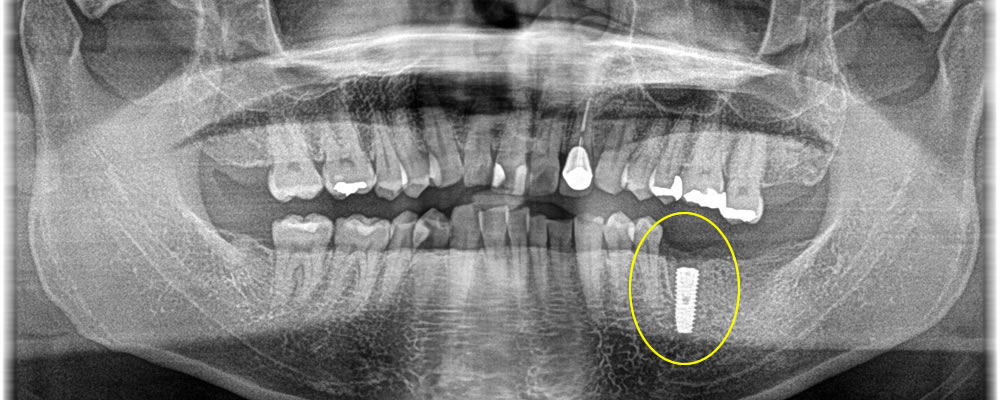

歯根が破折した歯を抜歯し、インプラントを埋入しました。インプラントの持ちをより良くするために骨造成も同時に行っています。